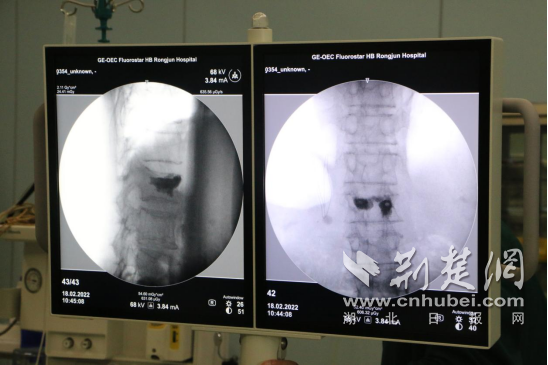

2月18日,手术开始。医生在患者背部切开黄豆大小的切口,通过穿刺针进入病变椎体内,利用球囊扩张增压让压缩椎体复位,将骨折部位撑开,注入配置好的骨水泥,恢复椎体高度。

“骨水泥可以增加椎体强度和稳定性,防止椎体塌陷,缓解疼痛。”术后,医生介绍,“注射过程须透视查看骨水泥的分布情况,防止骨水泥渗漏。”

手术现场。通讯员供图